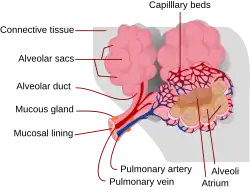

Pneumocyt je souhrnné označení pro několik typů plicních buněk. Název je odvozen z řeckého „pneumo-“ (πνεύμων, česky „plíce“). Pneumocyty se podílejí na stavbě plicních sklípků (alveol). Přímo nebo nepřímo zajišťují přenos plynů (kyslíku a oxidu uhličitého) mezi vzduchem v plicích a krví.

Tato buňka označovaná také jako membranózní pneumocyt nebo skvamózní alveolární buňka je extrémně tenká epiteliální buňka, která lemuje vnitřní povrch plicních sklípků. Všechny běžné organely (endoplazmatické retikulum, Golgiho aparát a mitochondrie) jsou nahloučeny kolem jádra.[1] Zde dosahuje pneumocyt tloušťky 4–6 μm. Od jádra pak vycházejí ztenčující se výběžky, které bývají 10–15 μm dlouhé a místy jsou jen 25 nanometrů tlusté. Výběžky obsahují pouze četné pinocytotické váčky. Buňky jsou napevno spojné pomocí dezmozomů a těsných spojů.

Výběžky pneumocytů I. typu tvoří součást tzv. alveolokapilární membrány – soustavy, která zajišťuje difuzi (průchod) kyslíku z vnitřku sklípků do krve[2] a naopak odvod oxidu uhličitého z krve do plic a odtud výdechem z organismu.

Pneumocyty I. typu tvoří asi 96 % povrchu plicních sklípků, ale představují jen asi 40 % buněk plicních sklípků.[3]

Tento pneumocyt (také granulární pneumocyt nebo velká alveolární buňka) je rozměrově menší buňka, která vyplňuje prostory mezi pneumocyty I. typu, a tvoří s nimi i stejné buněčné spoje. Má kuboidální (tj. přibližně krychlový) tvar. Vyskytuje se často v malých shlucích, zejména v místech, kde spolu hraničí plicní sklípky. Tvoří pouze asi 4% povrchu plicních sklípků, ale představuje až 60% z počtu buněk plicních sklípků.[3]

V těchto buňkách se nachází cytoplazma bohatá na váčky, které obsahují plicní surfaktant – látku, která snižuje povrchového napětí v plicních sklípcích.[2] Obsah těchto váčků je vylučován na vnitřní povrch sklípků, kde se rozprostře a podílí se na průniku kyslíku z plicních váčků do krve a odvádění oxidu uhličitého z krve do vydechovaného vzduchu.